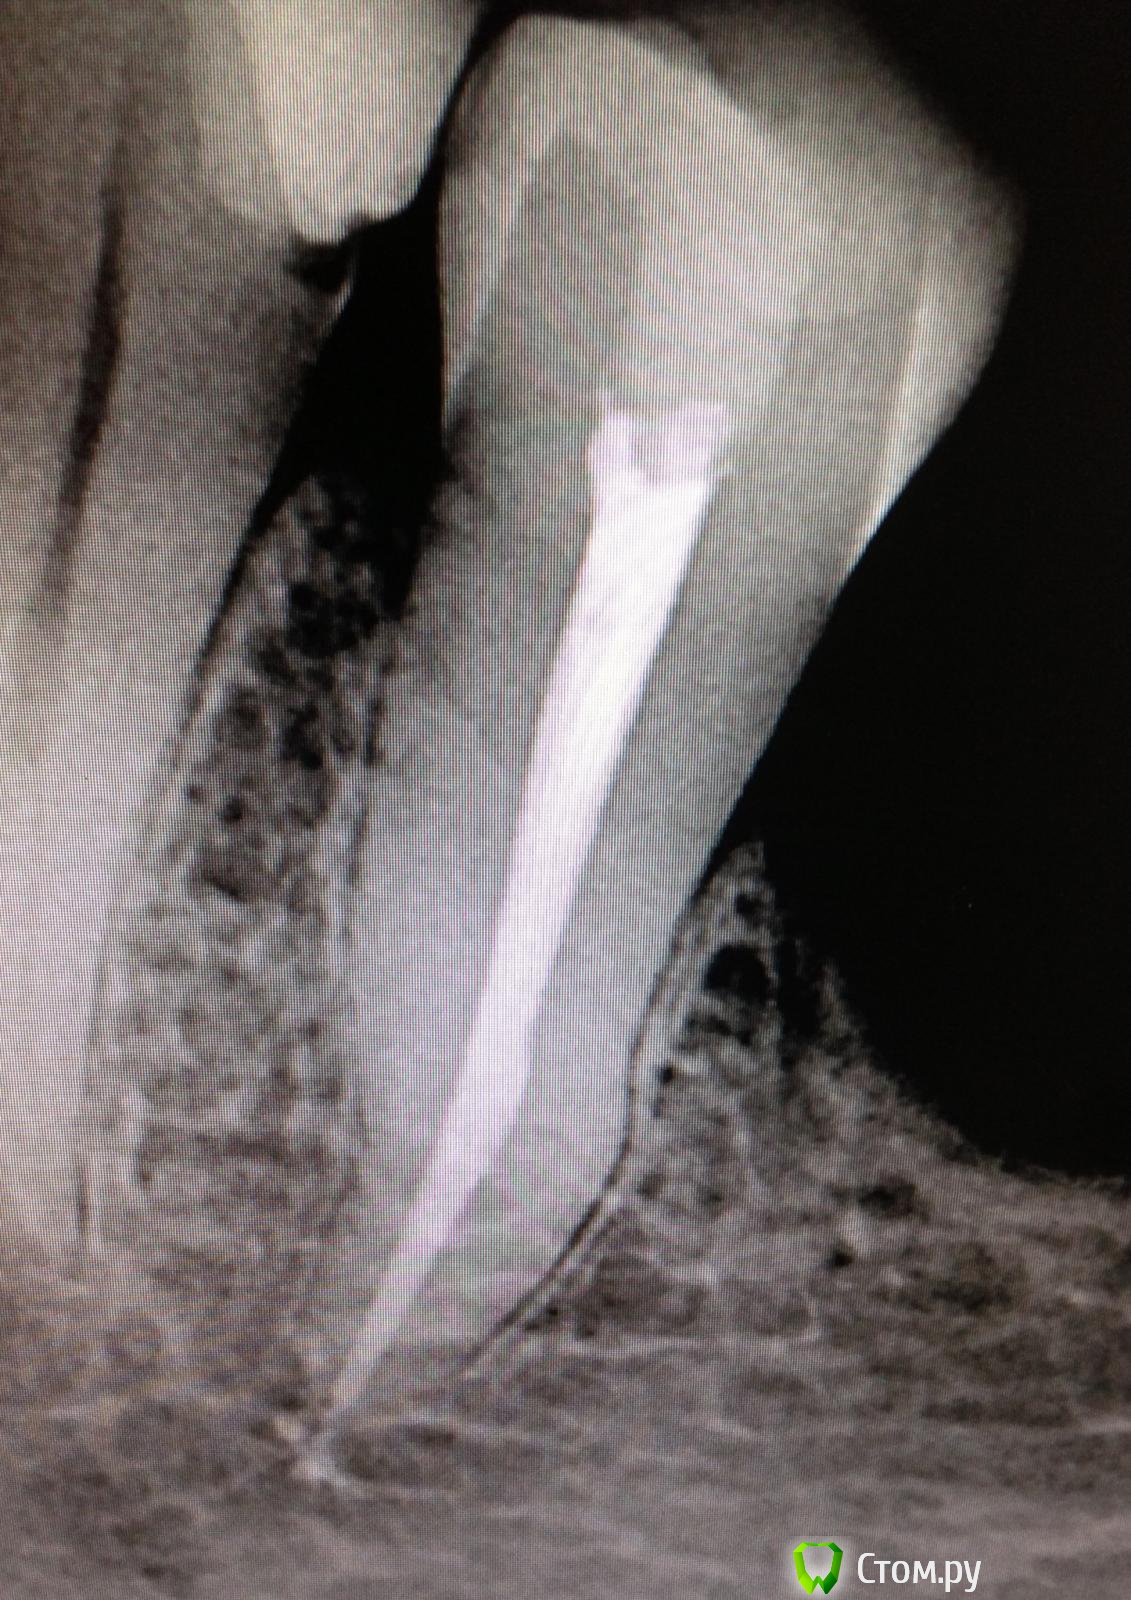

SSTi Опубликовано 26 мая, 2014 Автор Поделиться Опубликовано 26 мая, 2014 " Керамические "пульпиты( депульпировал по мк). 45. Дистально старая пломба. Доступ. Коффер. Протейперы машинные до ф2, профайлы, стоп упор 30.02. Гипохлор, аш два о, хлоргексидин. Уз. Латералка. 35. Стоп упор 40.02. Ссылка на комментарий